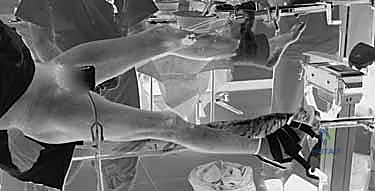

1. التخدير وتجهيز المريض

يبدأ الإجراء باختيار نوع التخدير المناسب (غالباً تخدير نصفي شوكي أو تخدير عام) بناءً على تقييم طبيب التخدير. يُنقل المريض إلى طاولة عمليات خاصة تُسمى (طاولة الكسور - Fracture Table). هذه الطاولة تسمح بشد الساق المصابة وتدويرها لرد الكسر (إعادته لوضعه الطبيعي) دون الحاجة لفتح جراحي كبير.

2. الرد المغلق (Closed Reduction)

باستخدام جهاز الأشعة السينية المرئية المستمرة (C-Arm Fluoroscopy) داخل غرفة العمليات، يقوم الدكتور هطيف بإعادة العظام المكسورة إلى محاذاتها التشريحية الصحيحة عن طريق الشد والتدوير الخارجي للساق، وكل ذلك يتم مراقبته على الشاشة بدقة متناهية.